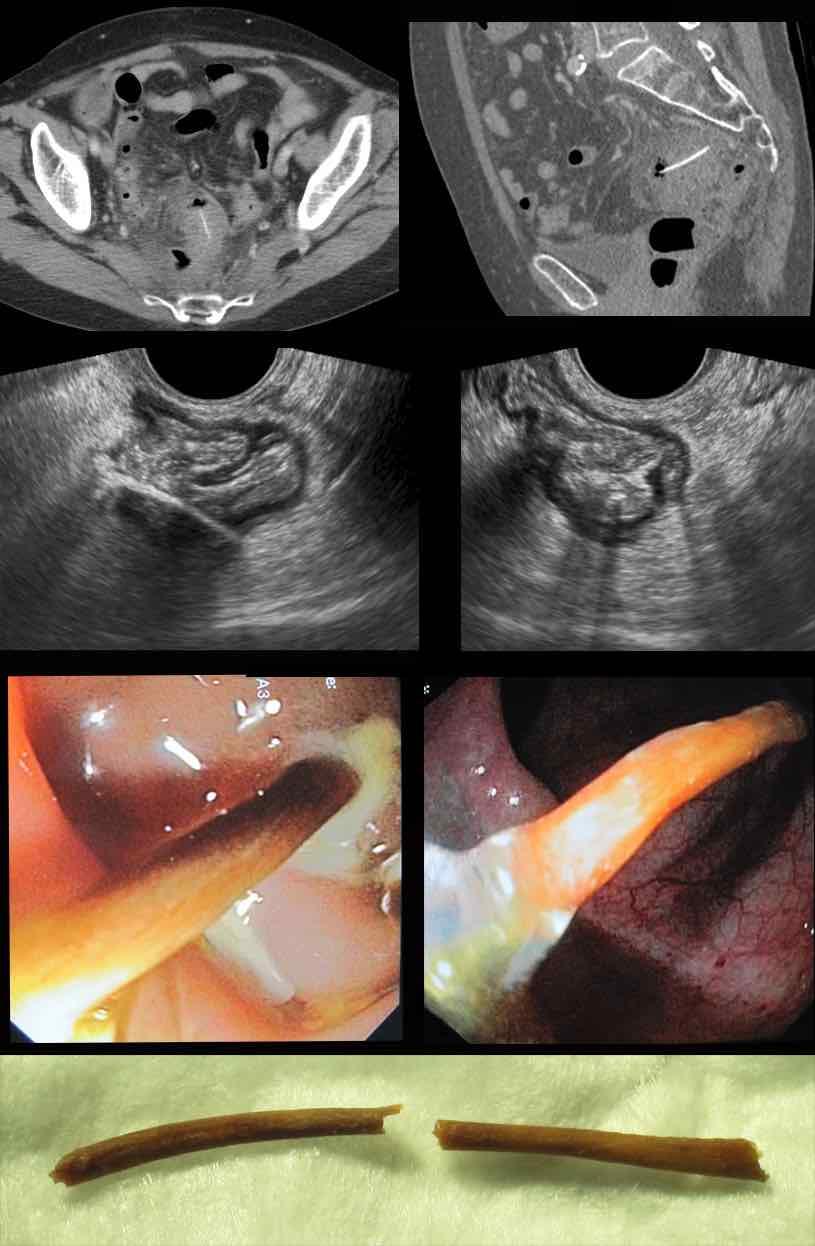

Bệnh nhân nữ 74 tuổi nhập viện với đau bụng dưới sâu kéo dài 3 tuần. Xét nghiệm: bạch cầu 15, CRP 150. Bệnh nhân có tiền sử nhiều lần phẫu thuật phụ khoa.

CT được thực hiện và phát hiện một dị vật dạng xương, với cả hai đầu đều có vẻ xuyên thủng đại tràng sigma.

Siêu âm qua đường âm đạo xác nhận dị vật đi xuyên qua lòng đại tràng sigma, do đó có thể lấy dị vật qua nội soi đại tràng.

Trong quá trình nội soi, xương gà phải được bẻ làm hai phần để lấy ra an toàn. Bệnh nhân hồi phục tốt với sự hỗ trợ của kháng sinh.

Bệnh nhân nam 33 tuổi này (có tiền sử cắt đoạn ruột lúc 4 tuổi) nhập viện với đau thượng vị và CRP 155. Siêu âm và CT xác nhận cấu trúc dạng xương (mũi tên) xuyên thủng quai ruột non có dính.

Qua đường mổ nhỏ (mini-laparotomy), một mảnh xương sắc dài 6 cm đã được lấy ra. Bệnh nhân đã ăn vịt Bắc Kinh hai ngày trước đó.